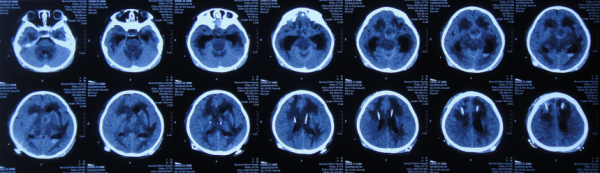

在第4家醫院治療26天期間內,三次複查頭部CT(圖-29、圖-30、圖-31)均示腦積水,右側顳角明顯擴。

圖-29:2020年4月23日頭部CT

圖-30:2020年5月7日頭部CT

圖-31:2020年5月18日頭部CT